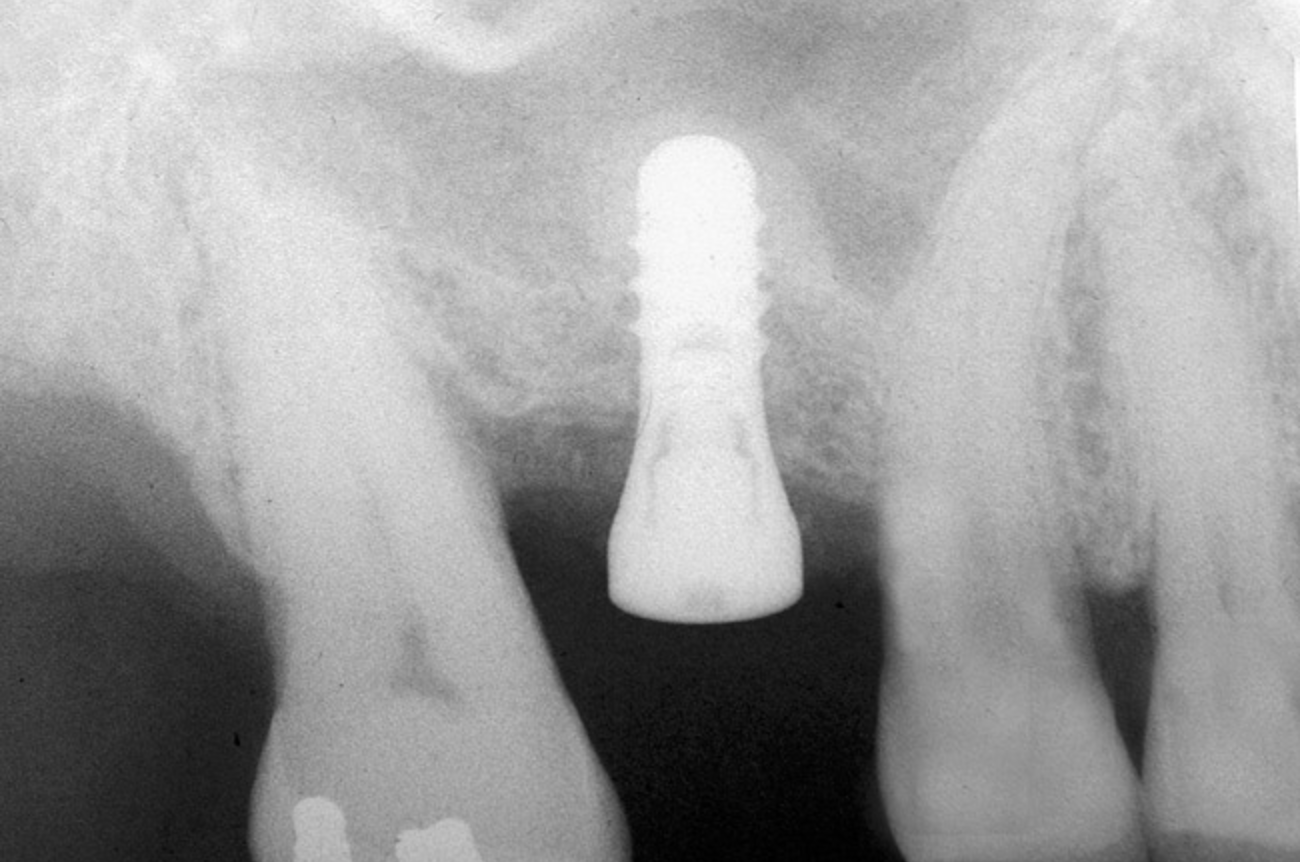

The 2-mm twist drill is used to create an osteotomy 1 mm short of the subantral floor. If any resistance is detected prior to reaching the 3-mm depth, drill penetration must be stopped, because the subantral cortical bone has possibly been reached. Any uncontrolled "push" would penetrate the bone and likely perforate the sinus membrane. A guide pin is then inserted and a radiograph taken to determine if drill penetration has terminated within 1 mm of the subantral floor (Figure 2). If the radiograph indicates that more than 1 mm of bone is present subantrally, the twist drill is used again to penetrate within 1 mm of the sinus floor. Alternately, an osteotomy tip for a piezosurgery unit can be used for this purpose. The final depth of penetration should be verified with another periapical film.

Figure 2  After drilling to a depth of 3 mm with a 2.1-mm twist drill, the guide pin was placed and a radiograph was taken to ascertain if the drill stopped within 1 mm of the subantral floor.

Figure 2